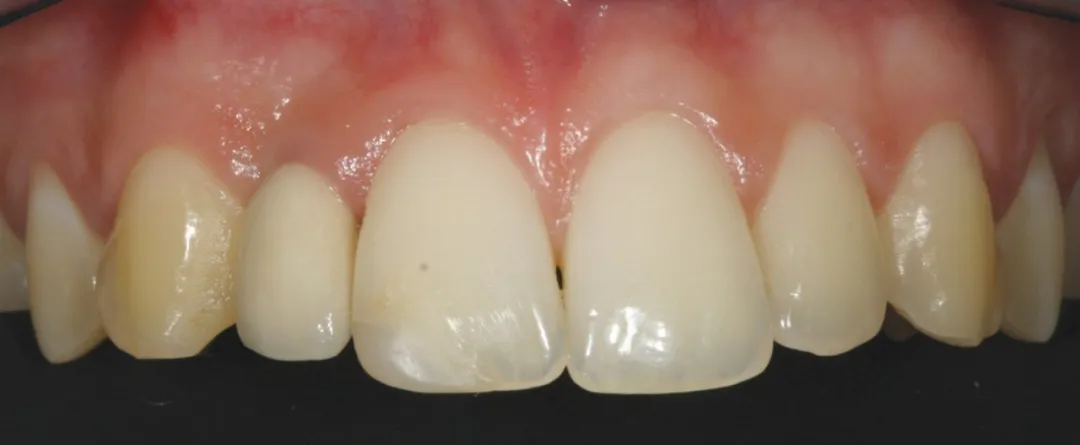

3 号病例 - Patrick EXBRAYAT 医生(图 36 至 49)

女性患者,侧切牙 12 发育不全,长期使用临时修复手段。

图 48 :术后 1 年口内情况。